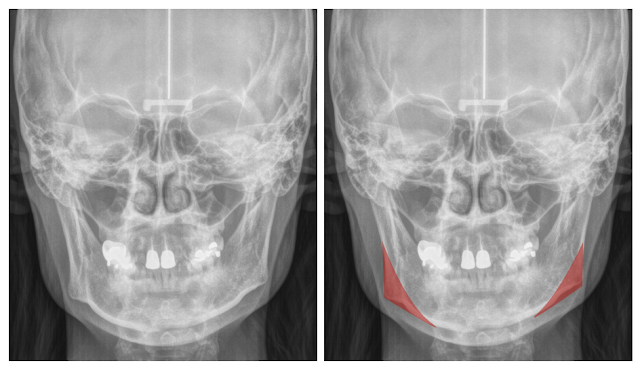

S小姐因為下臉較寬的問題困擾很久,一開始 Botox 治療覺得稍微有改善,但經過一陣子就覺得沒什麼效果。從 X ray可以看到明顯的下顎骨角是造成下臉較寬的原因,經由手術將下顎骨角縮小,不但臉部線條變得柔和,臉頰凹陷的問題也獲得改善。

療程效果因人而異,上圖為該案例實際術後成效